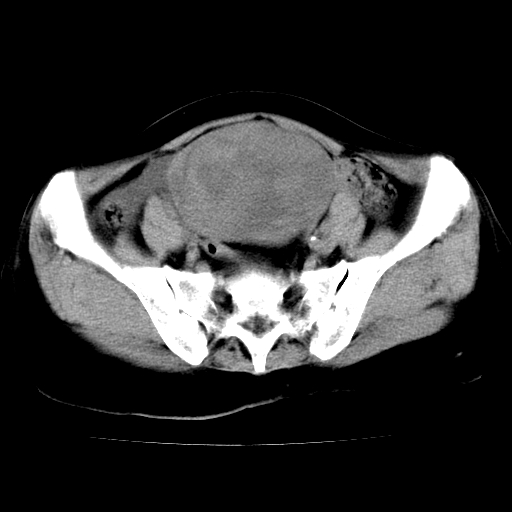

标题: CT24785:女,62岁,发现下腹部肿物半年。 [打印本页]

标题: CT24785:女,62岁,发现下腹部肿物半年。

女,62岁,发现下腹部肿物半年,下腹部不适。

老年女性患者,盆腔囊实性占位,ct增强不均匀强化,未见壁结节,未见腹水及盆腔积液,考虑附件囊腺瘤可能性大!

卵巢囊腺瘤或囊腺癌,建议免疫组化实验

卵巢囊腺瘤或囊腺癌可能。